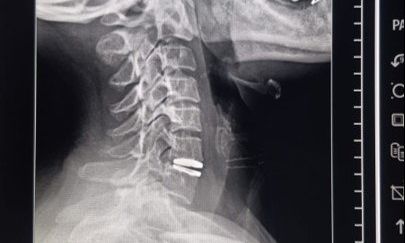

Realizaron el primer reemplazo de disco cervical con prótesis móvil en Villa Mercedes

Por primera vez en Villa Mercedes, profesionales del sistema público de salud realizaron un reemplazo de disco cervical con prótesis discal móvil, una cirugía de alta complejidad que preserva la movilidad cervical y evita procedimientos más invasivos. La intervención se concretó el lunes dentro de los nuevos quirófanos del policlínico ‘Juan Domingo Perón’ y constituye un hecho inédito para el sistema sanitario local.

La paciente, una mujer de 48 años oriunda de Fraga, presentaba dolor cervical con irradiación a hombros, con impacto funcional. El procedimiento estuvo a cargo de Sebastián Heredia, médico neurocirujano, junto con el equipo de instrumentación quirúrgica integrado por Virginia Mora e Ivana Altamirano.

Para la colocación de la prótesis discal móvil, participaron técnicos especializados de la ortopedia Zion Corpomedica, contratada por el ministerio de Salud a través de la dirección de Emergencia Sanitaria, dado que la paciente no cuenta con obra social. Todos los costos de la cirugía, la prótesis y la atención fueron asumidos por la cartera provincial.

La paciente evolucionó favorablemente y recibió el alta médica este martes, con recuperación clínica satisfactoria y preservación de la movilidad cervical.